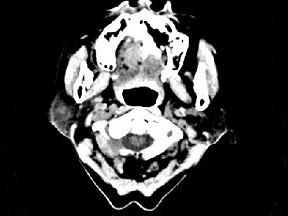

问题 女,72岁,六年前于右面颊部扪及一包块,缓慢增大,其表面较光滑,CT如图所示,该病例应诊断为 ( )

选项 A、颈部淋巴瘤 B、小唾液腺瘤 C、腮腺混合瘤 D、颈部神经纤维瘤 E、Worthin瘤

答案 C